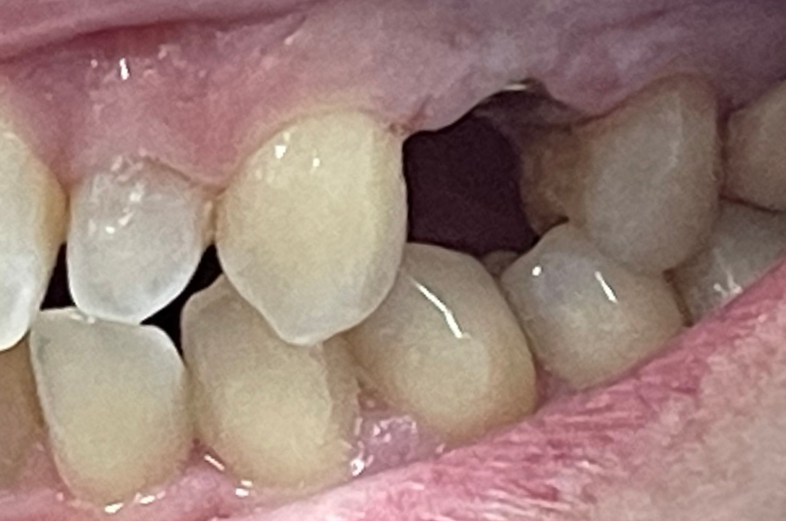

CHECK OUT THIS AWESOME RESULTS

(use cursor to move arrows left and right to see before and after images)